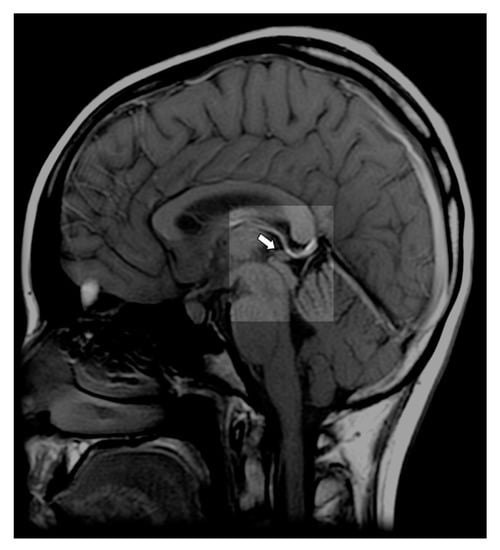

- Liebrich, L.S.; Schredl, M.; Findeisen, P.; Groden, C.; Bumb, J.M.; Nölte, I.S. Morphology and function: MR pineal volume and melatonin level in human saliva are correlated. J. Magn. Reson. Imaging 2014, 40, 966–971. [Google Scholar] [CrossRef]

- Tan, D.-X.; Manchester, L.C.; Reiter, R.J. CSF generation by pineal gland results in a robust melatonin circadian rhythm in the third ventricle as a unique light/dark signal. Med. Hypotheses 2016, 86, 3–9. [Google Scholar] [CrossRef]

- Reiter, R.J.; Tan, D.-X.; Kim, S.J.; Cruz, M.H.C. Delivery of pineal melatonin to the brain and SCN: Role of canaliculi, cerebrospinal fluid, tanycytes and Virchow-Robin perivascular spaces. Brain Struct. Funct. 2014, 219, 1873–1887. [Google Scholar] [CrossRef]